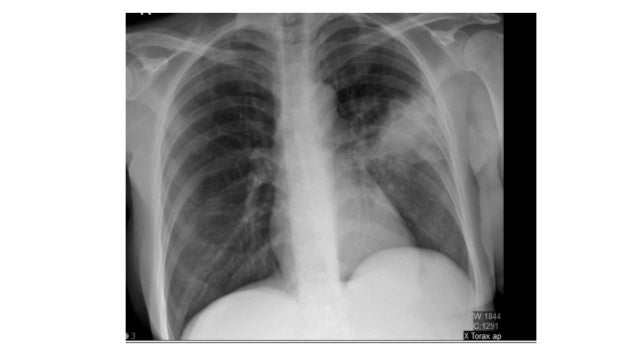

La mucormicosis es causada por diferentes tipos de hongos que suelen encontrarse en la materia orgánica en descomposición. Instituto de oftalmología fap conde de valenciana, iap ®. La mucormicosis es una infección rara y grave con hongos del orden. De wikipedia, la enciclopedia libre. Ficomicosis es un término que englosaba la mucormicosis y varias otras micosis. La #mucormicosis puede ser mortal en pacientes con sistemas inmunológicos débiles. La mucormicosis es una infección por hongos potencialmente mortal. Muy útil para el diagnóstico de. La infección se presenta con mayor frecuencia en personas que tienen un sistema. Afecta los senos, el cerebro o los pulmones. Mucormicosis.) y bien inducido, este último es. Otras observaciones positivas permiten una orientación terapéutica (mucormicosis, aspergilosis, etc.). These molds live throughout the environment.